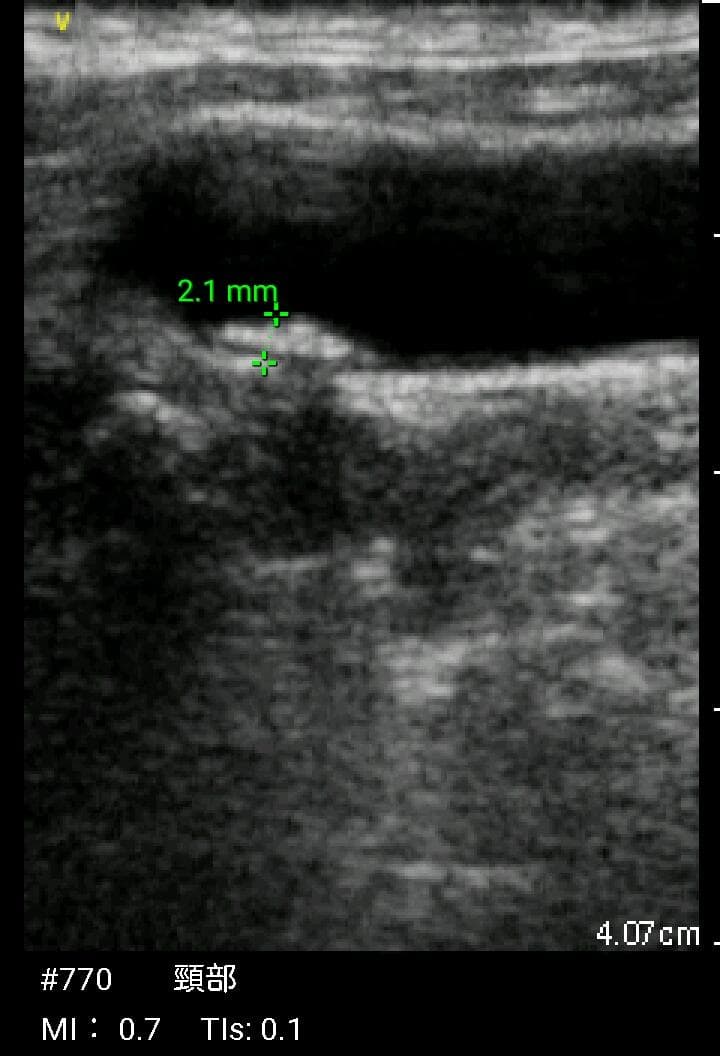

おわかりになる方のみの購入をお願いいたします実際に実施した写真をあげました正常肝臓、胆石症、頸動脈プラーク、同じく頸動脈プラーク、Mrの収縮期、同じくM弁の開放期とA弁の開放期、腹部大動脈瘤、正常の頸動脈、甲状腺右葉の結節、前立腺肥大画像の描出は条件によりますがご検討をお願いいたします経年変化、使用に伴うスレや傷などがあります機能に問題はありませんスキャンは心血管、腹部、体表に対応します外部接続端子のカバーが一部壊れていますが蓋は閉まりますバッテリーはフル充電されますが劣化はあると思います医療用モニタリング機器 Vscan Extend、GE- モデル名: Vscan Extend- ブランド: GE- 色: ホワイト- 機能: 医療用モニタリング機器ご覧いただきありがとうございます。鈴木 ALCARE Youcare-TDc 医療用テープ 25mm 6個。